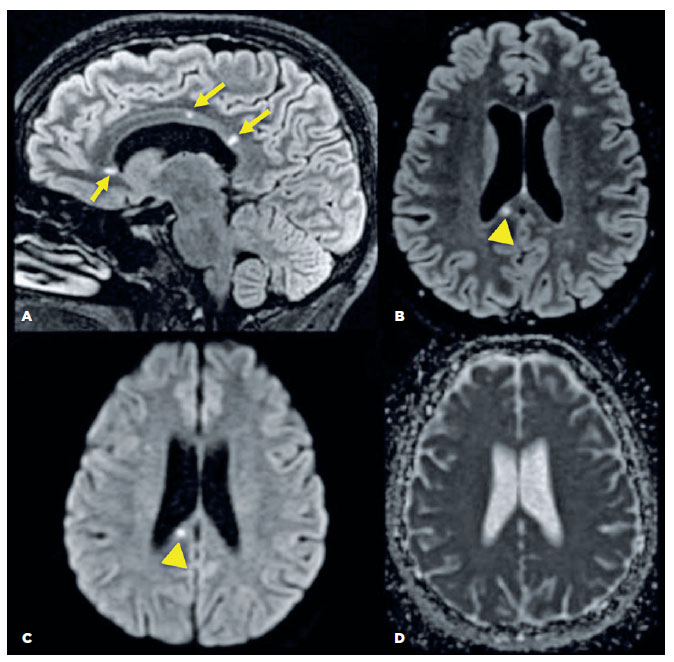

A brain MRI of the patient revealed small spherical high-signal intensity lesions on FLAIR and T2 sequences. These were located within the fiber tracts of the corpus callosum, with no ependymal undersurface involvement. The dominant lesion in the splenium showed restricted diffusion indicative of a small ischemic infarct (Figure 3).